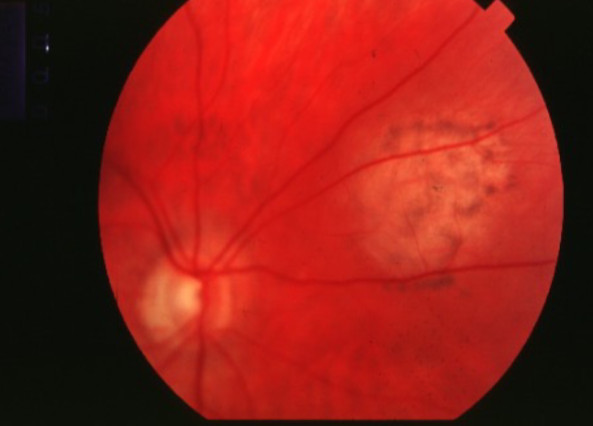

choroidal melanoma

melanoma

melanoma

melanoma

melanoma

melanoma

melanoma

melanoma

melanoma

melanoma

melanoma

melanoma

melanoma

melanoma

melanoma

melanoma

melanoma